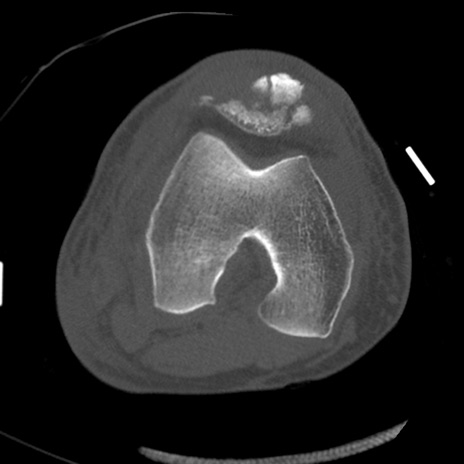

症例28 右膝関節CT(横断像)

右膝関節CT